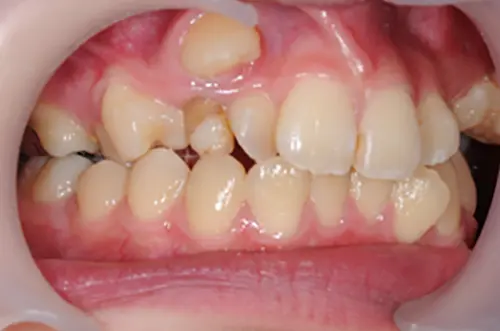

一般的な八重歯の症例

一般的な八重歯のケースであれば、マウスピース矯正で十分に改善が見込めます(※1)。八重歯は専門的には「叢生(そうせい)」や「乱杭歯(らんぐいば)」の一種とされ、顎のスペース不足により歯が正しい位置に収まりきらず、列からはみ出してしまった状態を指します。

マウスピース矯正では、歯列全体を奥歯側へ移動させたり、歯の側面をわずかに削ってスペースを作ったりすることで、はみ出した八重歯を正しい位置に誘導します。軽度から中程度の八重歯であれば、インビザラインなどをはじめとするマウスピース矯正システムが得意とする動きで対応できることが多いです。